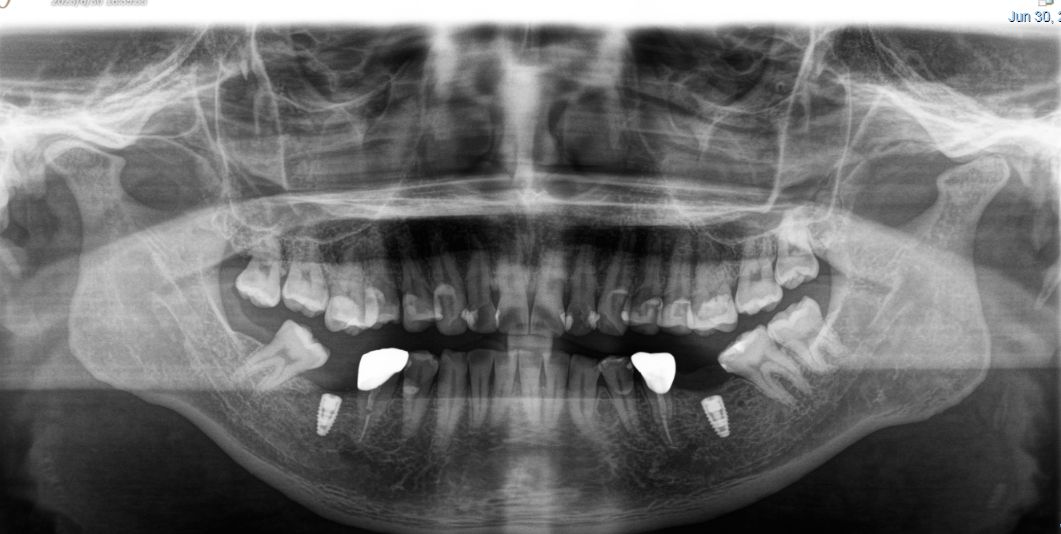

患者男,四十四岁,36,46缺失已植入种植体,附着龈不足,缺牙区牙槽嵴呈刀刃状,缺牙区咬合间隙及近远中间隙尚可。可行游离牙龈移植术增宽种植体周围附着龈的面积。